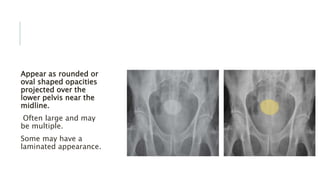

Appear as rounded or

oval shaped opacities

projected over the

lower pelvis near the

midline.

Often large and may

be multiple.

Some may have a

laminated appearance.